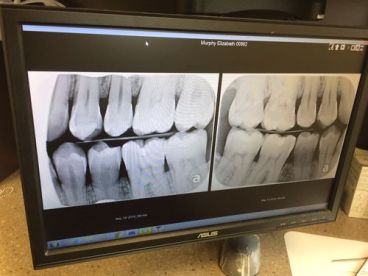

I was off today and as I do on most Thursdays, I spent time with my adorable little mother. What is one of the most enjoyable things anyone could do on their day off? Yup, go to the dentist. Woot! I actually don’t mind going at all. I’m happy to report, I am officially 40 years cavity free! Check out these adorable teeth:

Hi there Miss Perfect Teeth..!

Wow that is something to be proud of for sure..!!! I am a benefactor of inherited poor teeth… I do my best to keep them up but my mouth is full of amalgam fillings and porcelain and gold crowns. they say the human body is only worth a few dollars in the raw materials it is comprised of… NOT ME..!!! I’m several thousand in precious metals alone..!!